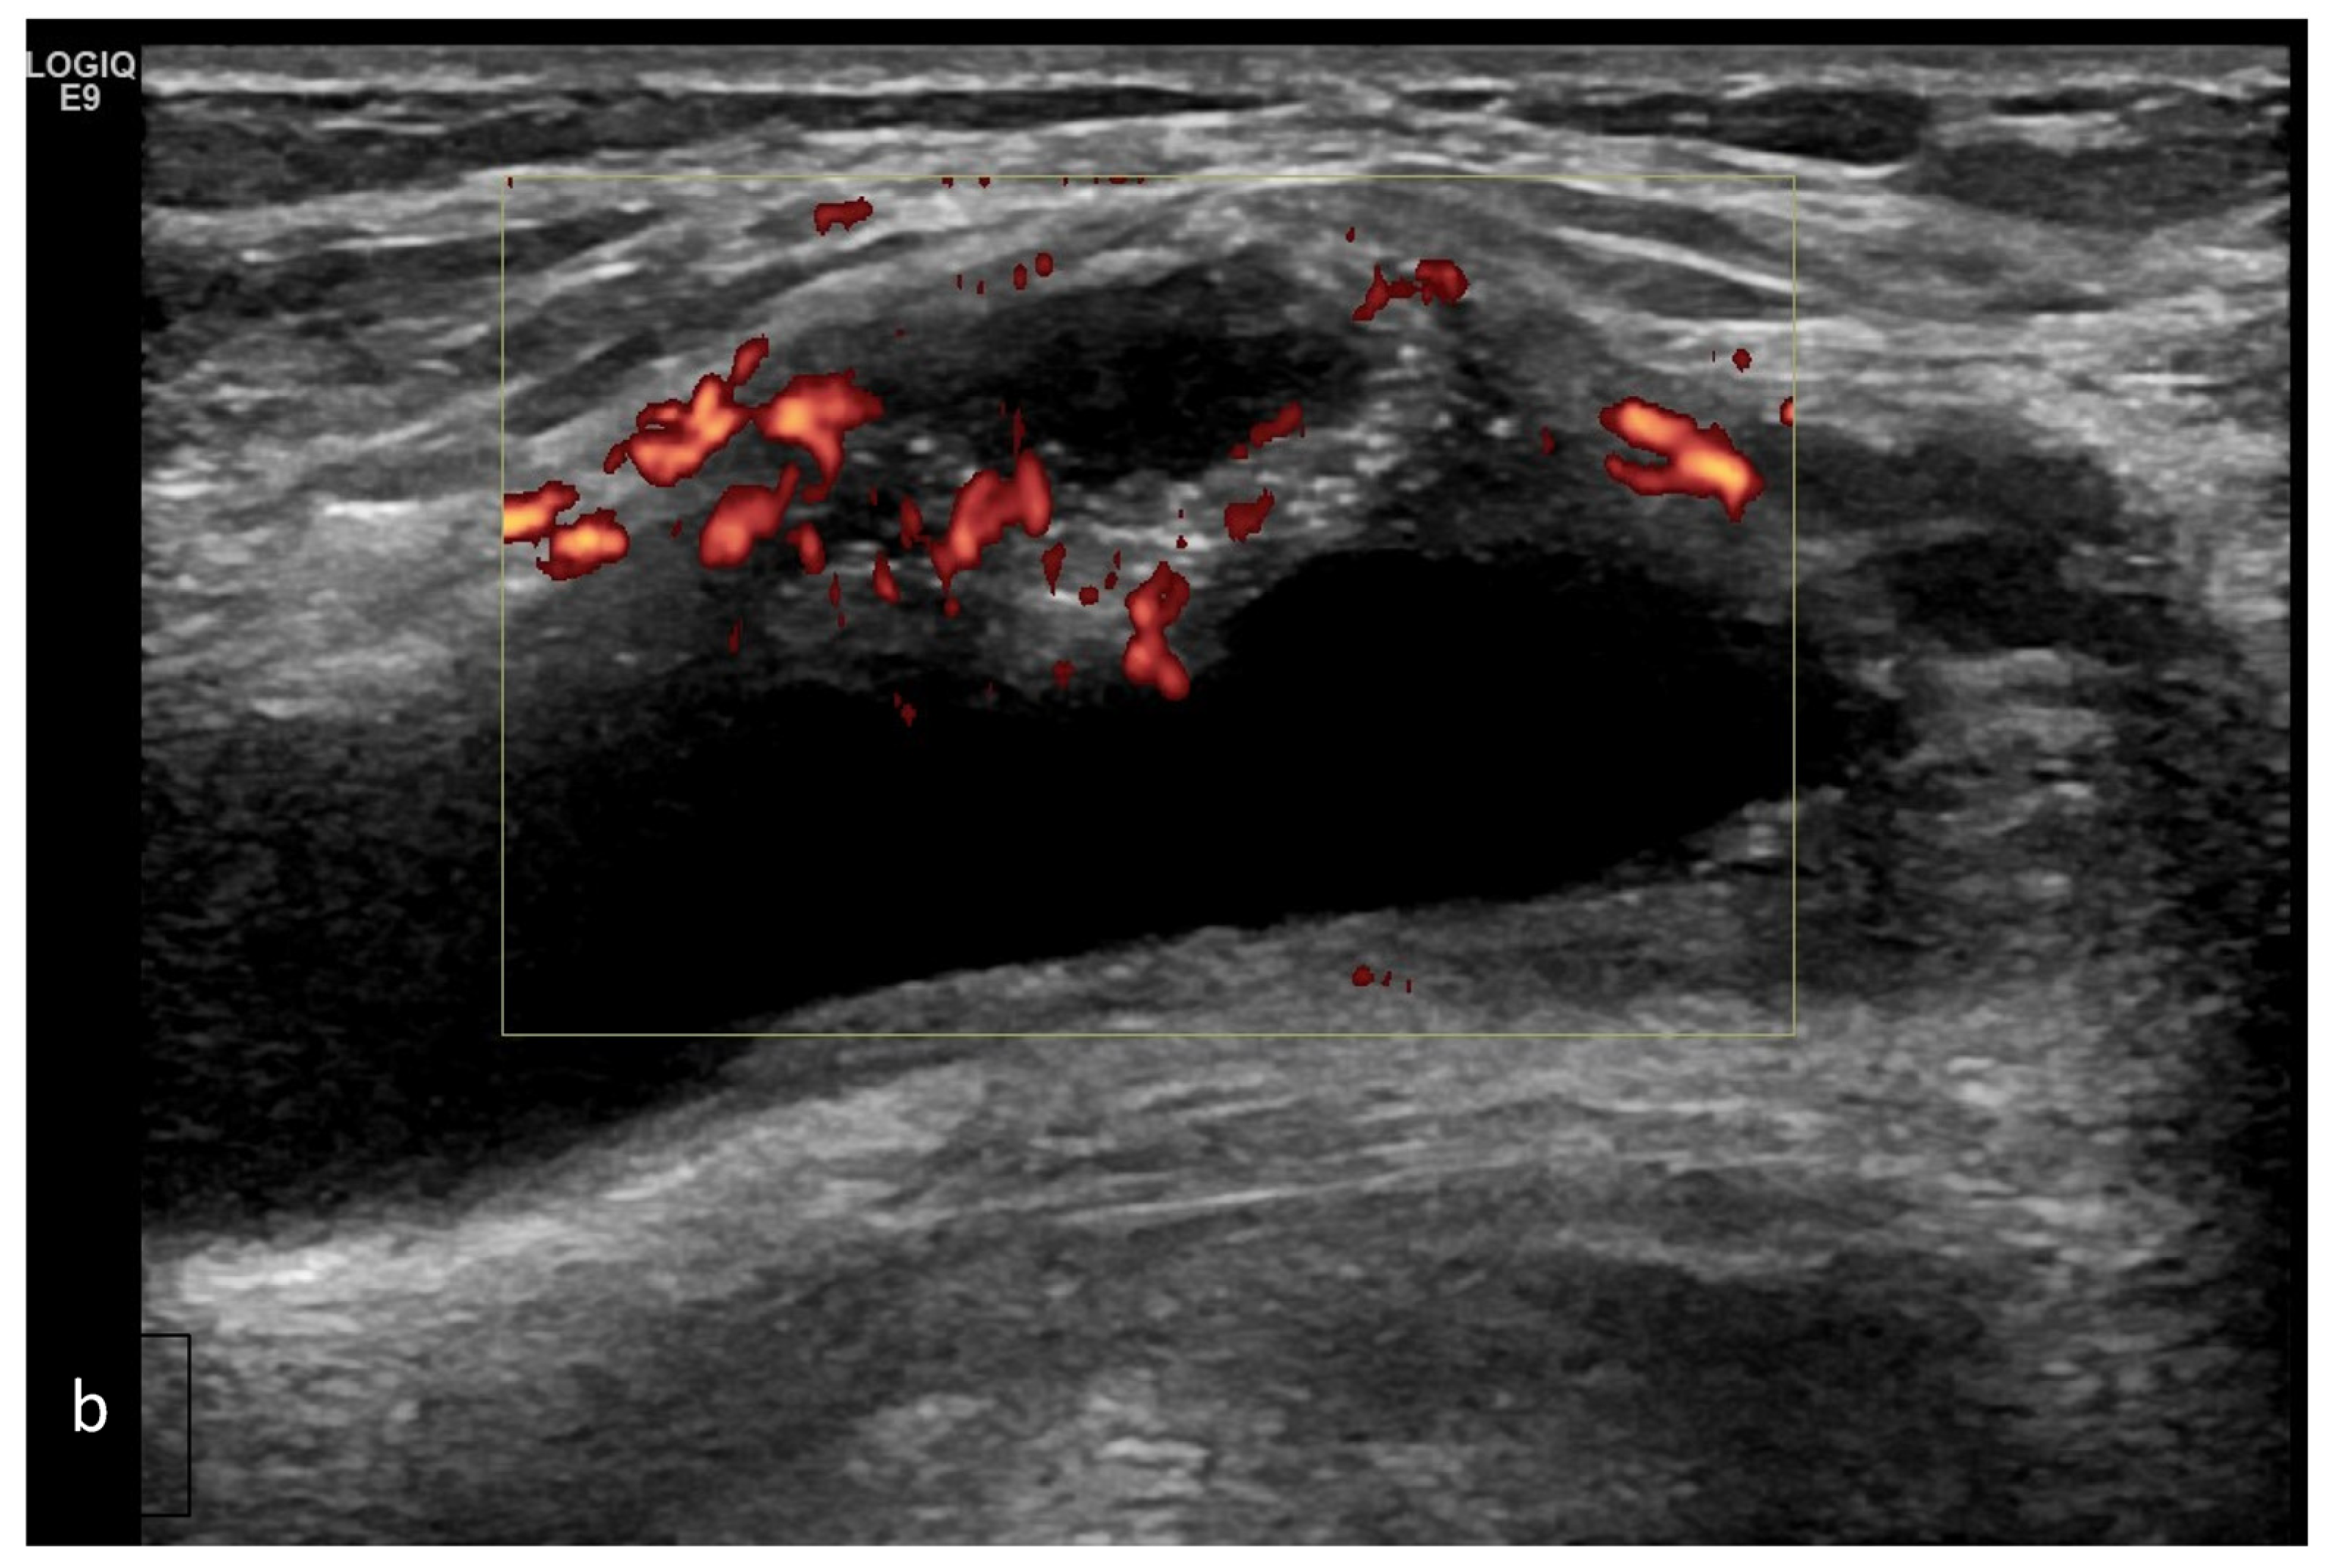

- Predominant synovial proliferation, fat pads, and Hoffa synovitis (with a small amount of intra-articular effusion);

- Predominant cartilage destruction (with almost no synovitis and intra-articular effusion);

- Altered subchondral bone (superficial bone erosions or osteophytes);